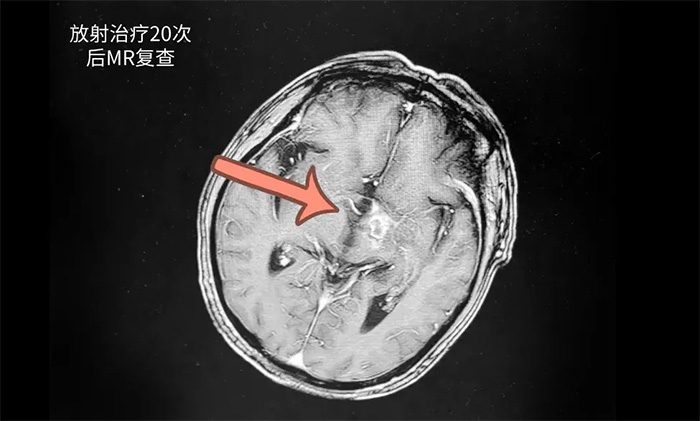

王曉東主任團隊為患者完善各項檢查。根據(jù)患者的臨床資料、病理診斷和影像結(jié)果,明確患者滿足放療條件,并制定了完善周密的放療計劃。為患者開展20次放射治療。歷時約1個月完成治療后,患者頭暈、頭痛,伴言語不清等癥狀有了不同程度改善。復(fù)查頭顱MR,可見病灶范圍明顯縮小。

▲ 復(fù)查顯示病灶范圍明顯縮小